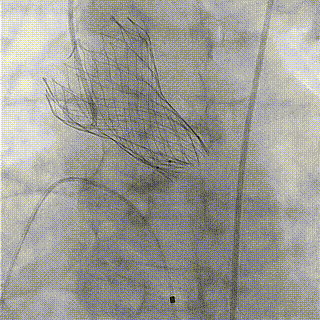

瓣膜释放

球囊后扩

目前,经导管主动脉瓣置换术已成为重度主动脉瓣狭窄及关闭不全患者改善症状和预后的有效治疗策略。厦门大学附属心血管病医院在该领域不断创新,勇于挑战,无论手术量及手术难度都处于国内领先地位。此次主瓣置换手术,充分展示了国产自主品牌启明第三代可回收瓣膜Venus-A Pro的通过性和更好的操作性,完美演绎了应用结构性心脏病领域瓣膜置换最新器械治疗高危复杂的手术病例。厦心结构性团队将继续在王焱教授的领导下,孜孜不倦,尽心竭力,为广大老年瓣膜性心脏病患者带来更多的帮助。